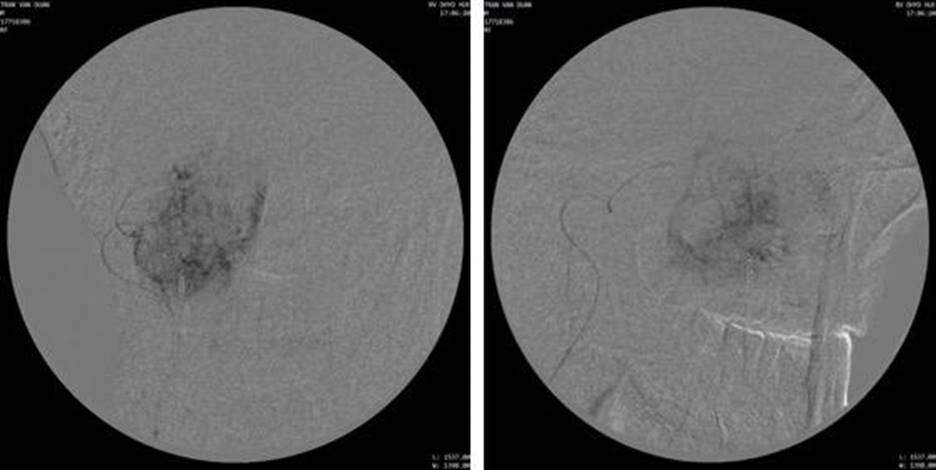

Chụp động mạch cảnh ngoài bên phải thấy khối u ở xoang hàm phải lan rộng, tăng sinh mạch, cấp máu từ nhánh động mạch mũi ngoài (lateral nasal artery) của động mạch mặt và động mạch huyệt răng sau trên (posterior superior aveolar artery) của động mạch hàm.

Chọn lọc nhánh nhánh động mạch mũi ngoài bằng vi ống thông (microcatheter Asahi 1.98F), chụp hình các mặt phẳng thẳng và nghiêng để xác định hình ảnh u ngấm thuốc (tumor staining) và nguồn cấp máu cho khối u. Nút mạch ngoại vi bằng hạt PVA contour 250-355μm, nút gốc động mạch mũi bằng 1 microcoil 2x70mm. Chụp kiểm tra thấy tắc hoàn toàn nhánh nuôi u.

Hình 3: Chụp động mạch mặt phải và chụp chọn lọc nhánh tận động mạch mũi ngoài, khối u ngấm thuốc mạnh, tăng sinh mạch trong u (hypervascularity)

Hình 4: Chụp kiểm tra sau nút mạch bằng hạt PVA và microcoil không còn thấy hình ảnh u ngấm thuốc